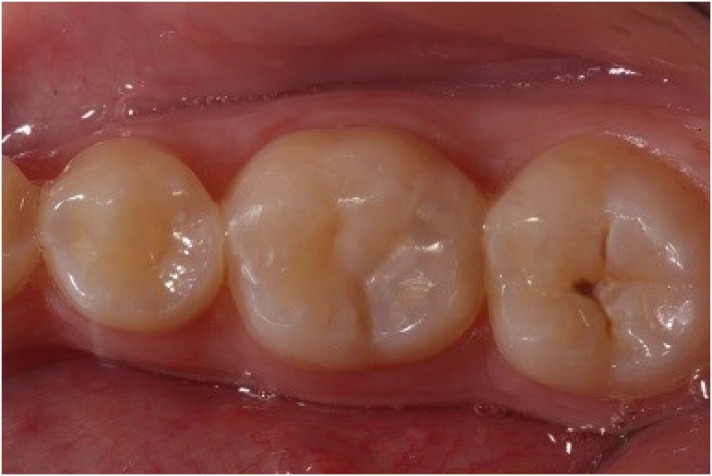

Figure 7

Composite Bulk Fill Restoration placed after finishing and polishing procedures.

rde-45-e9-g007.jpg